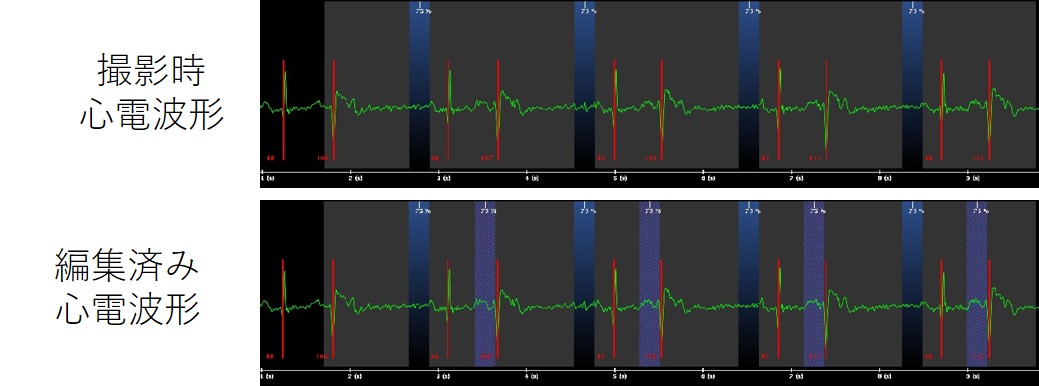

冠動脈CT前のホルター心電図検査をしたところ、多源性PVC、連続した不整脈も多く見られ、撮影時も心室性期外収縮が多発しておりました。

撮影データを確認するとブレが大きく(図7(上))、検査終了後の副作用確認・説明の際に、造影検査時のみ息止めがほとんどできなかったといわれた症例です。

Frontier_Kofukyoritsu10.jpg

不整脈を削除した上で動きの少ない位相でSSF2を掛けたところ、図7(下)にまでバンディング影響を抑えることが出来ました。どうしてもバンディングの出てしまったLADは、より動きの少なかった別位相のデータで補完するなどの工夫で評価可能な画像を提出ことができました。

更新前の装置で撮影した際には、息止めができた検査でも冠動脈のブレが多く評価困難だったためカテーテル検査が必要になっていました。今回は息止め不良という悪条件が重なったにもかかわらず、CTのみで冠動脈の評価を行うことができました。